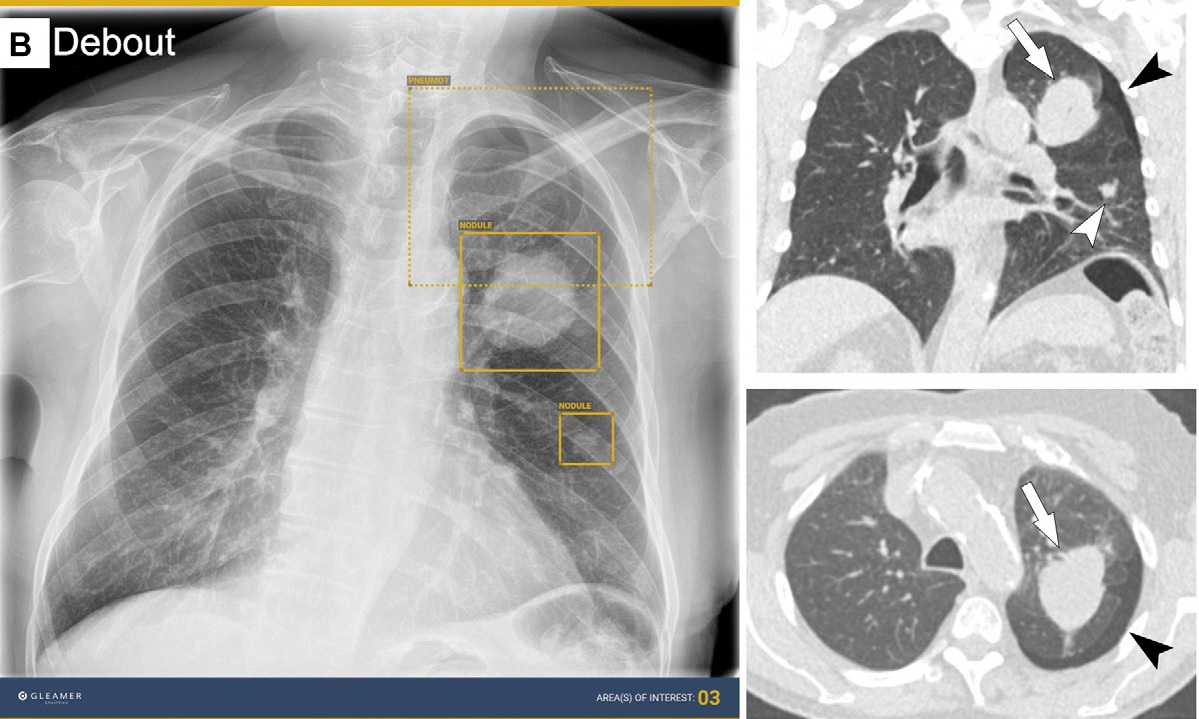

AI for thoracic imaging includes using it for reading chest radiographs and low-dose chest CT scans for lung cancer screening and for triaging pulmonary embolism on chest CT scans, the group noted. Other potential uses researchers are investigating are filtering out normal chest radiographs, monitoring reading errors, and automated opportunistic screening of incidentally identified disease.